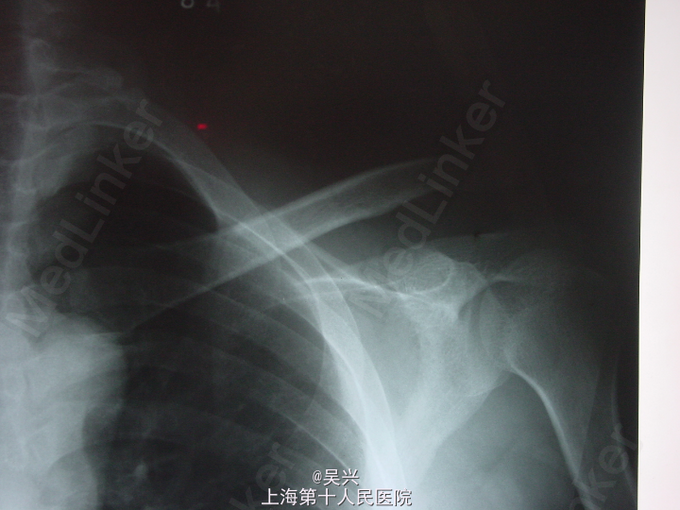

男,40岁,左肩贴伤肿痛、活动受限2小时急诊入院。

查体:左肩肿胀、畸形、触痛,活动受限。 辅查:X线片提示左肩锁关节三度脱位。